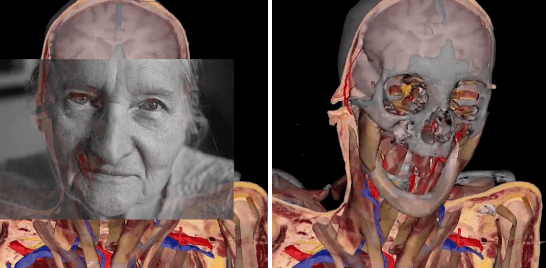

2000 yılında doktorlar Sue'ya sadece 1 yıllık ömür biçmişlerdi. Fakat vücudunu bağışlayan kadın 15 yıl daha yaşadı ve bu süreç içinde sık sık hastaneyi ziyaret etti.

Sue bu ziyaretlerinde hem tıp öğrencileri ile tanışıyor hem de öldükten sonra vücudunun nasıl kesip fotoğraflanacağı hakkında daha detaylı bilgi alıyordu.